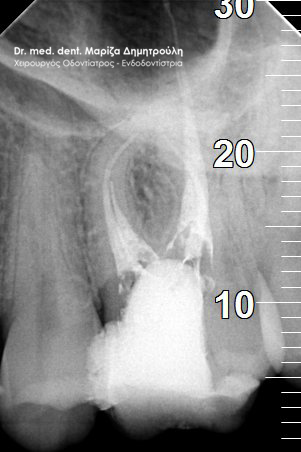

Στον ασθενή είχε πραγματοποιηθεί σε συνάδελφο ένα λευκό σφράγισμα στο αριστερό δεύτερο γομφίο της άνω γνάθου. Από τότε το δόντι εμφανίζει μέτρια (κατά διαστήματα έντονα) συμπτώματα πόνου, σε βαθμό που να μην επιτρέπει στον ασθενή να φάει με άνεση. Στην κλινική εξέταση το δόντι έδινε έντονα και ξεκάθαρα συμπτώματα πόνου στην επίκρουση. Η ακτινογραφία αποκάλυψε οτι το σφράγισμα ίσως να είχε τοποθετηθεί κοντά στο νεύρο του δοντιού, γεγονός που μπορεί να ερέθισε τον πολφό του δοντιού γι αυτό και πονούσε.

Η θεραπεία επιλογής στο συγκεκριμένο περιστατικό ήταν η απονεύρωση δοντιού. Η ενδοδοντική θεραπεία ολοκληρώθηκε σε δύο ραντεβού και το δόντι είναι πλέον ασυμπτωματικό. Η αποκατάσταση του δοντιού πραγματοποιήθηκε με λευκό σφράγισμα, εφόσον το έλλειμμα των οδοντικών ιστών δεν ήταν μεγάλο για να απαιτείται η προστασία του δοντιού με θήκη / στεφάνη.

ΠΡΙΝ

ΜΕΤΑ